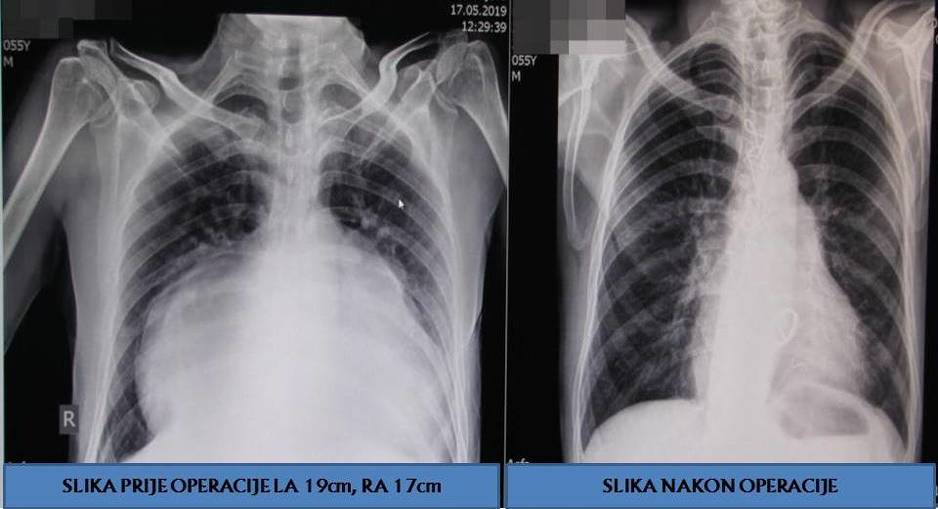

"Pacijent Hasanović javio se na Kliniku za kardiovaskularnu hirurgiju KCUS nakon što je ostao bez glasa, sa uznapredovalom formom strukturne bolesti srca. Pored primarne bolesti, u toku dijagnostičke obrade ustanovljena je i ishemijska bolest srca. Iako je od rane mladosti bio upoznat da ima bolesno srce, on je prilagođavajući stil života, potiskujući tegobe i zanemarujući simptome, dugi niz godina odlagao operativno liječenje. Prije deset godina je uslijed embolizacije desne karotidne arterije, preležao i težak moždani udar, nakon kojeg se dugo oporavljao. Gigantske pretkomore, nastale uslijed dugotrajne bolesti srčanih zalistaka su vršile kompresiju na pluća i ostale strukture u grudnom košu, izazivajući kod Sabrije hronično stanje teške srčane i respiratorne insuficijencije. Nakon sprovedene dijagnostike i pažljivog planiranja, izveli smo kombinovanu operaciju strukturne i ishemijske bolesti srca, koja je uključivala tehniku eksplantacije srca, ex vivo resekcije i rekonstrukcije srca, zamjenu i reparaciju oštećenih zalistaka, reimplantaciju srca, odnosno autotransplantaciju srca, a potom i revaskularizaciju srca", pojašnjava doc.dr.Granov.